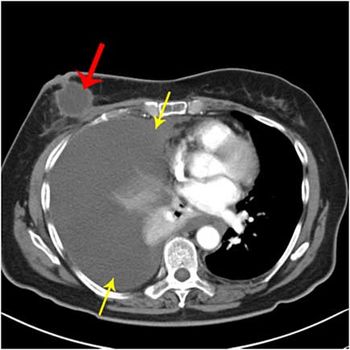

Clinical History: An 81-year-old female was admitted to the hospital with a chief complaint of shortness of breath. Image 1: Note the pleural fluid filling the right lung and circumscribed mass in the right breast.